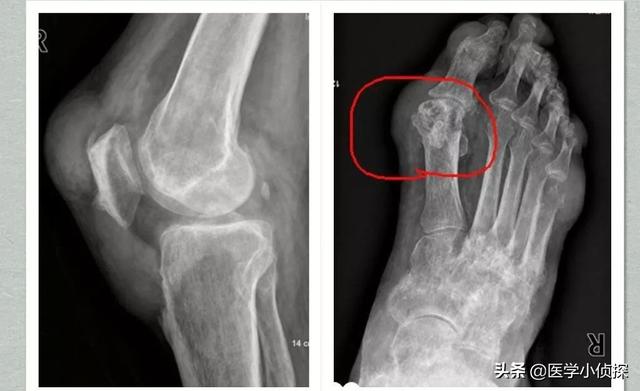

第2段階は、例えば超音波検査で「ダブルトラックサイン」を検出したり、画像検査を行うことである。デュアルエナジーCTで尿酸塩沈着が見つかるなど、そしてX線検査で軟部組織の腫脹、軟骨辺縁の破壊、関節面の不整が認められる。!

第3段階は、冒頭で述べた関節痛などの臨床症状とともに、基本的には確定診断につながる。

痛風は画像診断で発見することができ、関節軟骨の「ダブルトラックサイン」関節液貯留、骨びらんなどの有無、腎機能指標でも診断することができる。

- (10) 左右非対称の関節内腫脹(X線で確認)

- (11) 骨びらんを伴わない骨皮質下嚢胞(X線で確認)